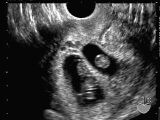

ikiz gebelik

Yumurtlama esnasında bir ya da iki yumurtalıkta birden fazla sayıda oosit hücresi olgunlaşır ve bu hücreler döllenirse çoğul gebelik meydana gelir. Eğer döllenme iki ayrı sperm ve iki ayrı oositle olursa çift yumurta ikizi oluşur. Bu bebeklerin cinsiyeti aynı olabileceği gibi farklı da olabilir, genetik yapıları birbirinden farklıdır ve birbirlerine ancak farklı zamanlarda dünyaya gelen kardeşler gibi benzerler. Tek bir oositin döllenmesi sonrasında bu döllenen hücrenin ikiye ayrılması ve ayrı ayrı canlılar olarak çoğalmasıyla ikiz oluşursa bu durumda tek yumurta ikizi söz konusu olur. Tek yumurta ikizlerinin genetik yapısı birbiriyle tamamen aynıdır. Bu yüzden de cinsiyetleri, kan grupları, saç, göz rengi gibi genetik olarak belirlenmiş özellikleri birbiriyle aynıdır.